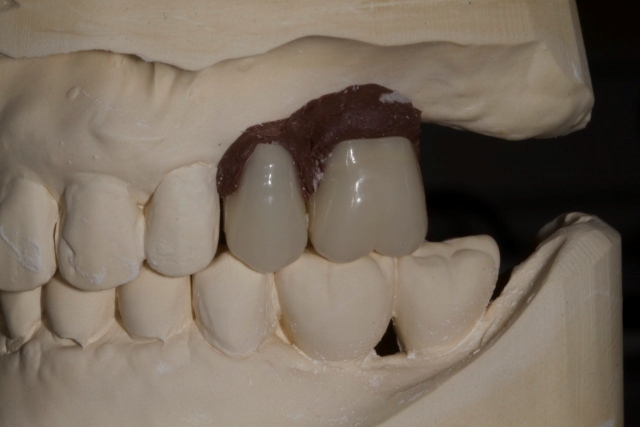

2. Complete a diagnostic wax-up or place denture teeth of an appropriate size in the restorative space. Use weather-stripping compound or autopolymerizing epoxy to hold the denture teeth in place or make a model of the wax mock up.

3. Using 1.5 mm clear splint material, do a vacuform over the denture teeth or model of the wax-up.

4. The appliance should then be trimmed so that the desired gingival levels of the final restorations are intact. The remaining teeth should be trimmed back so that 1-2 mm of overlapping acrylic remains to stabilize the template. This is an important landmark for the surgeon.

5. Using a radiopaque self-curing methylmethacrylate mixed to a putty consistency, fill the space left by the denture teeth or wax-up.

6. Trim the excess acylic back to the gingival margins.